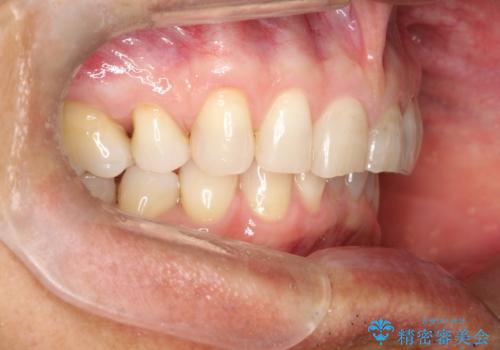

上の前歯の隙間とがたつきをインビザラインできれいな歯並びへ

- 以前矯正治療を他院にて行っており、最近上顎の隙間とガタガタが気になるとのことで来院されました。

上顎のみインビザラインにて矯正治療を行うこととなりました。

使用時間を守っていただけたので、比較的スムーズに矯正を終了することができました。